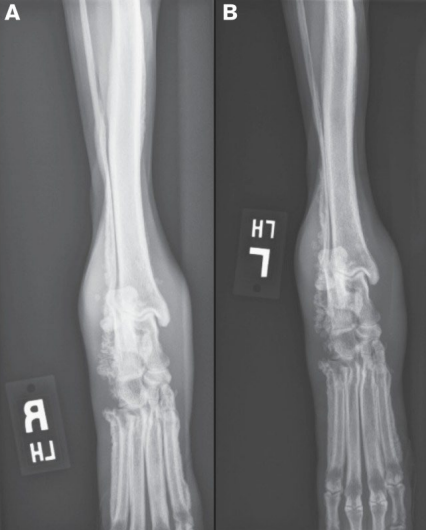

![]() | X-ray - ์ฌ์ง์์ ๊ท ์ผํ ๊ณจ๋ง ์ฆ์(uniform periosteal proliferation). - ์ฒ์์ Phalanges & metacarpal & metatarsal bones์์ ๊ด์ฐฐ๋จ. - ์งํ๋จ์ ๋ฐ๋ผ ๊ณจ๋ง ์ฆ์์ proximal(ulnar/radius, tibia/fibula)๋ก ์งํ๋จ. - Long bone์ ๊ด์ ํ๋ฉด์ ๋ณดํต ์ ์์ ์ผ๋ก ๋ณด์. |

![]() | - Firm soft tissue swelling of the distal extremities; ๋ง๋จ ์ฌ์ง์ ๋จ๋จํ ์ฐ์กฐ์ง ๋ถ์ข

ํ์ฑ. - ์์ชฝ, ๋์นญ์ ์ผ๋ก ๊ณจ๋ง ์ธ๋ถ์ ์ ์ ์กฐ์ง ํ์ฑ๋จ - ์ด๊ธฐ์๋ metatarsal/carpal bones์ ์ถ ์๋์ชฝ(abaxially)์์ ๊ด์ฐฐ. - ๋ผ์ ์ถ์ ๋ง์ฑ์ ์ธ ๊ฒฝ์ฐ ์ํฅ์ ๋ฐ์. |